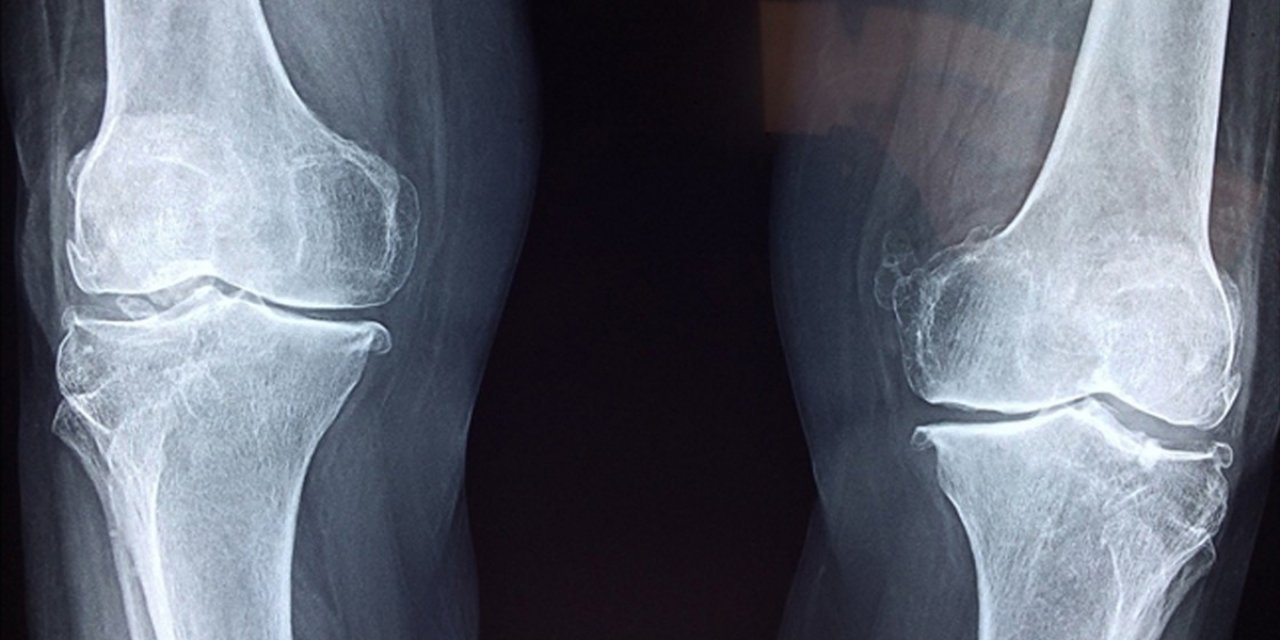

"Bilimsel çalışmalar, vücudun ihtiyacı olan kolajenin, morina ve gelincik balıklarının derilerinden elde edilebildiğini gösterdi. Morina balığı içerdiği prolin, histidin, glisin ve hidroksiprolin aminoasit zincirleri ile özellikle eklem ve kemikler için eşsiz bir fayda sunar. Bu aminoasitler sayesinde kıkırdak onarımı için çok etkili olduğu bilinen kolajen peptitler, aynı zamanda ağrı ve iltihaplanmayı azaltmada da önemli rol oynar. Yapılan çalışmalarla morina balığından elde edilen kolajen peptitlerin eklem ve kemik rahatsızlıklarında ağrı ve iltihabı azaltıp kıkırdak dokusunu yenilediği, iltihap azaltıcı özellikleri sayesinde akne ve selülit tedavilerine destek olduğu, nemlendirme ve kırışıklık önleyici özellikleriyle yaraların kapanmasını hızlandırıp iz oluşumunu engellediği bulgularına ulaşıldı."